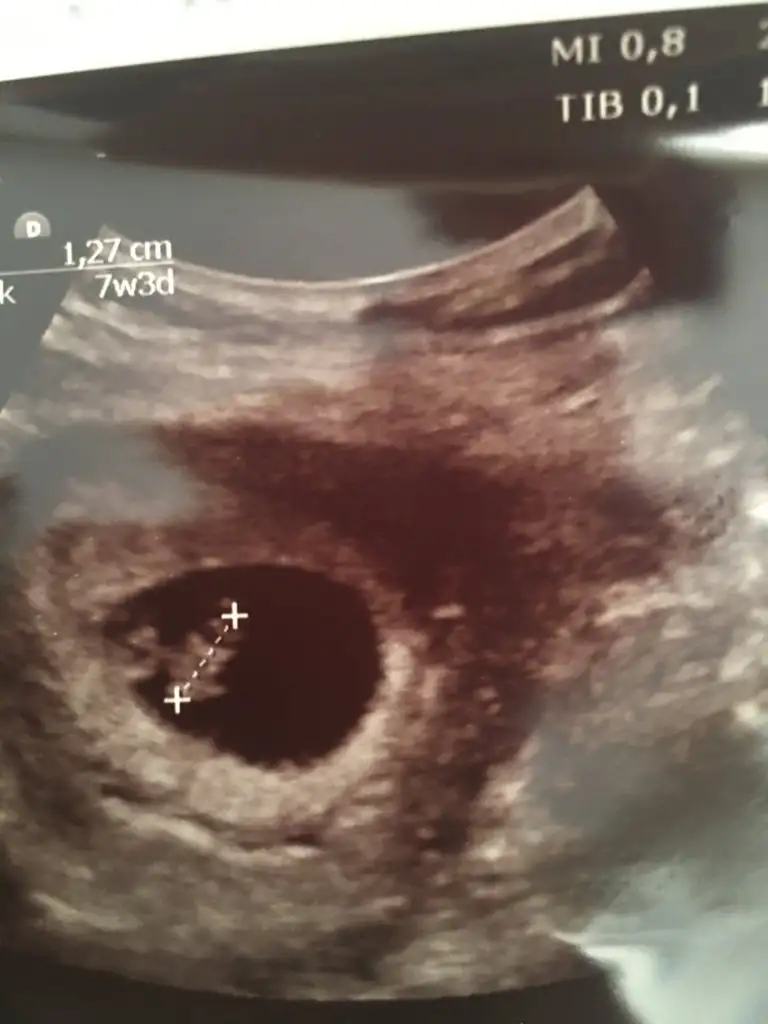

Merhaba benimde karından 7+3 yorumlarmısınız rica etsem 🥰

Eklentiler

• AB796D42-F996-48AC-8D3A-EA6903BE5F39.webp

AB796D42-F996-48AC-8D3A-EA6903BE5F39.webp

21,5 KB · Görüntüleme: 81